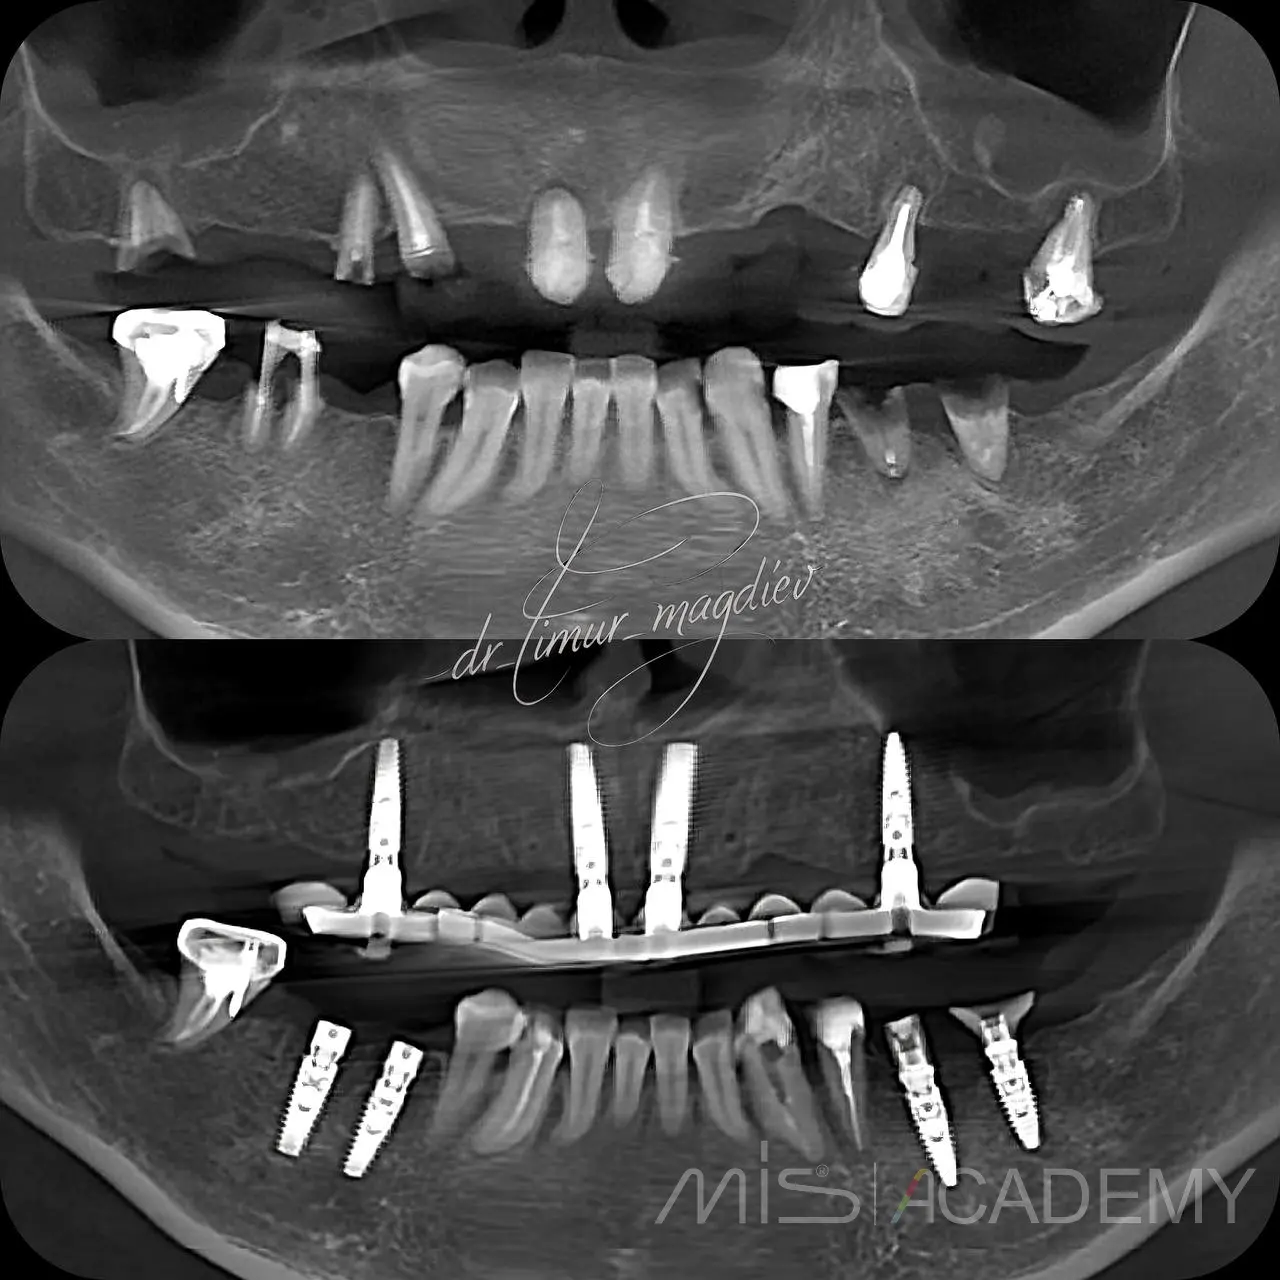

Комплексная реабилитация MIS Multi-fix.

— Циркониевая конструкция на 4х имплантатах.

Ортопед: Белобородцев Сергей Александрович.

Хирург: Тимур Магдиев